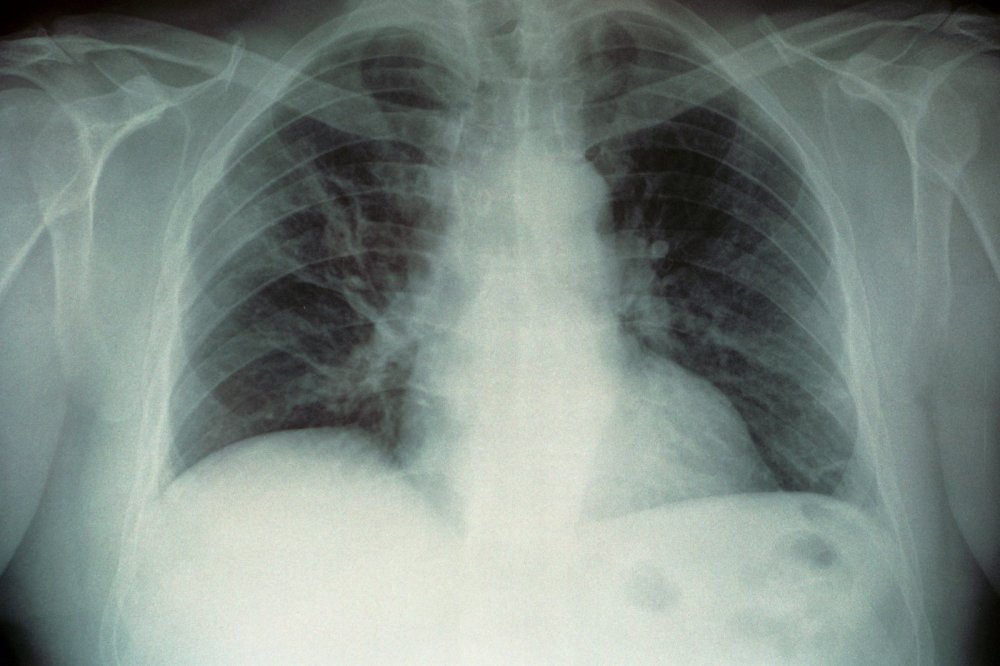

Legionela raste u vodi na temperaturi od 20 do 45 stupnjeva Celzijusa, idealnoj za mnoge umjetne vodne sustave. Bakterija se najčešće prenosi udisanjem kapljica zaražene vode koje sadrže legionelu. Nakon udisanja ulazi u pluća te se može brzo razmnožavati i izazvati upalu.

Simptomi legionarske bolesti mogu varirati od blagih do teških, često nalikujući simptomima gripe ili teške upale pluća. Tipični simptomi uključuju: